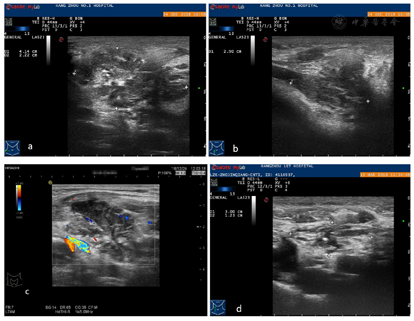

患者,男性,30岁,因"触及颈部无痛性包块1个月"就诊。体格检查:于右颈部可触及3.0 cm×2.0 cm的肿块,质韧,活动度差。浅表超声示:甲状腺双侧叶体积增大,内见多个散在的低回声结节,大者2.8 cm×1.4 cm×2.5 cm,边界光整,外形规则,内部回声欠均匀,彩色多普勒示结节内血流信号不丰富;右侧颈部可见一不均质回声团,大小约4.1 cm×2.9 cm×2.2 cm,边界模糊,外形不规则,CDFI示团块内可见散在条线状血流信号。为明确甲状腺及颈部软组织肿块性质,分别对甲状腺结节及颈部软组织进行粗针穿刺活检:因甲状腺双侧叶多个结节的超声声像图特点类似,故选取了右侧叶其中一个较大结节进行粗针穿刺活检。在超声引导下,用18G100 mm穿刺针各分3次穿入甲状腺右侧叶结节及右颈部软组织肿块,各取得苍白色组织3条。